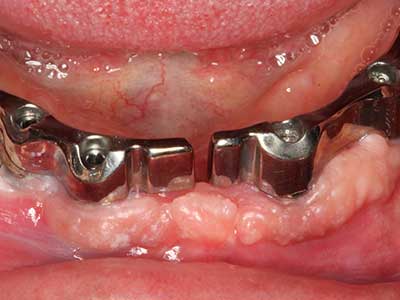

Die Präparation des lateralen Fensters bei der externen Sinusbodenelevation stellt gerade für chirurgisch unerfahrene Implantologen eine große Herausforderung dar. Die knöcherne Bedeckung der Kieferhöhle ohne eine Verletzung der darunterliegenden Schneider’schen Membran abzutragen ist dabei nur ein Teil der Operation – nach Schaffung eines ausreichenden Zugangs muss die Kieferhöhlenschleimhaut vorsichtig mobilisiert werden, um Raum für das einzubringende Material bzw. die Implantate zu schaffen. In dieser Indikation ist die Piezochirurgie zweierlei hilfreich: zum einen kann durch Verwendung diamantierter Instrumente eine selektive Knochenabtragung erfolgen und die darunter liegende Schleimhaut bleibt bei vorsichtiger Vorgehensweise intakt. Zum anderen unterstützen die Ultraschallfrequenzen zusätzlich eine komplikationslose Ablösung der Schleimhaut – sie werden durch spezielle stumpfe Ansätze in den Spaltraum zwischen Schleimhaut und Kieferhöhlenboden übertragen (Cassetta, Ricci et al. 2012, Pereira, Gealh et al. 2014) (Rickert, Vissink et al. 2013). So erscheint es nicht verwunderlich, dass in aktuellen Übersichtsarbeiten über die externe Sinusbodenelevation neben der Verwendung von rauen Implantatoberflächen und dem Einsatz von Knochenersatzmaterialien auch der Einsatz von piezoelektronischen Geräten als positiv bewertet wird (Wallace, Tarnow et al. 2012).